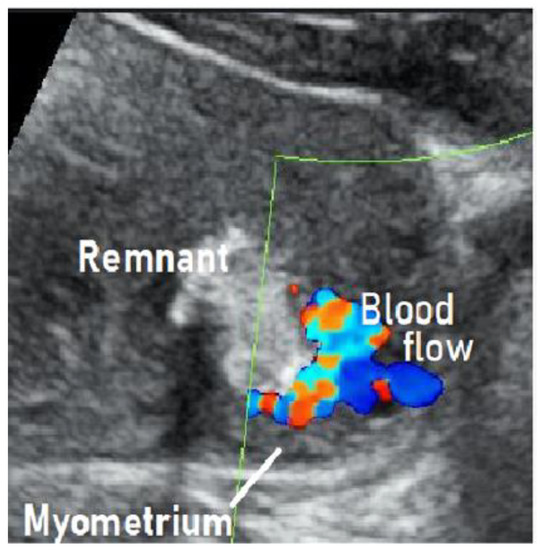

Angiography demonstrated abnormal engorgement in the arterial phase, with a thick venous phase visualized only 2 s later. This indicated the presence of an arteriovenous shunt, and an AVM with a hypervascular region was diagnosed (Figure 2) [20].

There was no pulsatile arterial perfusion in the remnant itself, where the contrast agent simply appeared to be leaking. The remnant was not the primary locus of the disease, but it was rather acting as a cover preventing major bleeding from the AVM. This case was correctly diagnosed as an AVM rather than RPOC with vascularization. UAE was performed, after which the remnant detached spontaneously, and the uterus was preserved.

Figure 2. Findings of angiography: Abnormal engorgement in the arterial phase, with a thick venous phase visualized only 2 s later. This indicated the presence of an arteriovenous shunt. There was no pulsatile arterial perfusion in the remnant itself, where the contrast agent simply appeared to be leaking.